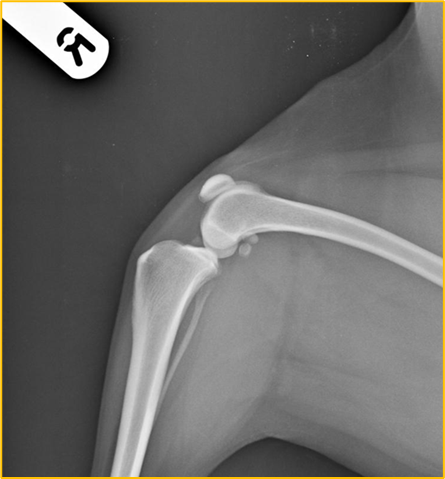

What is the centre point for this radiograph? - patient is in right lateral recumbency for a medio-lateral view of the stifle joint

The stifle joint

What are the collimation borders for this radiograph? - patient is in right lateral recumbency for a medio-lateral view of the stifle joint

Cranial and caudal skin edges, mid-shaft femur and mid-shaft tibia and fibula